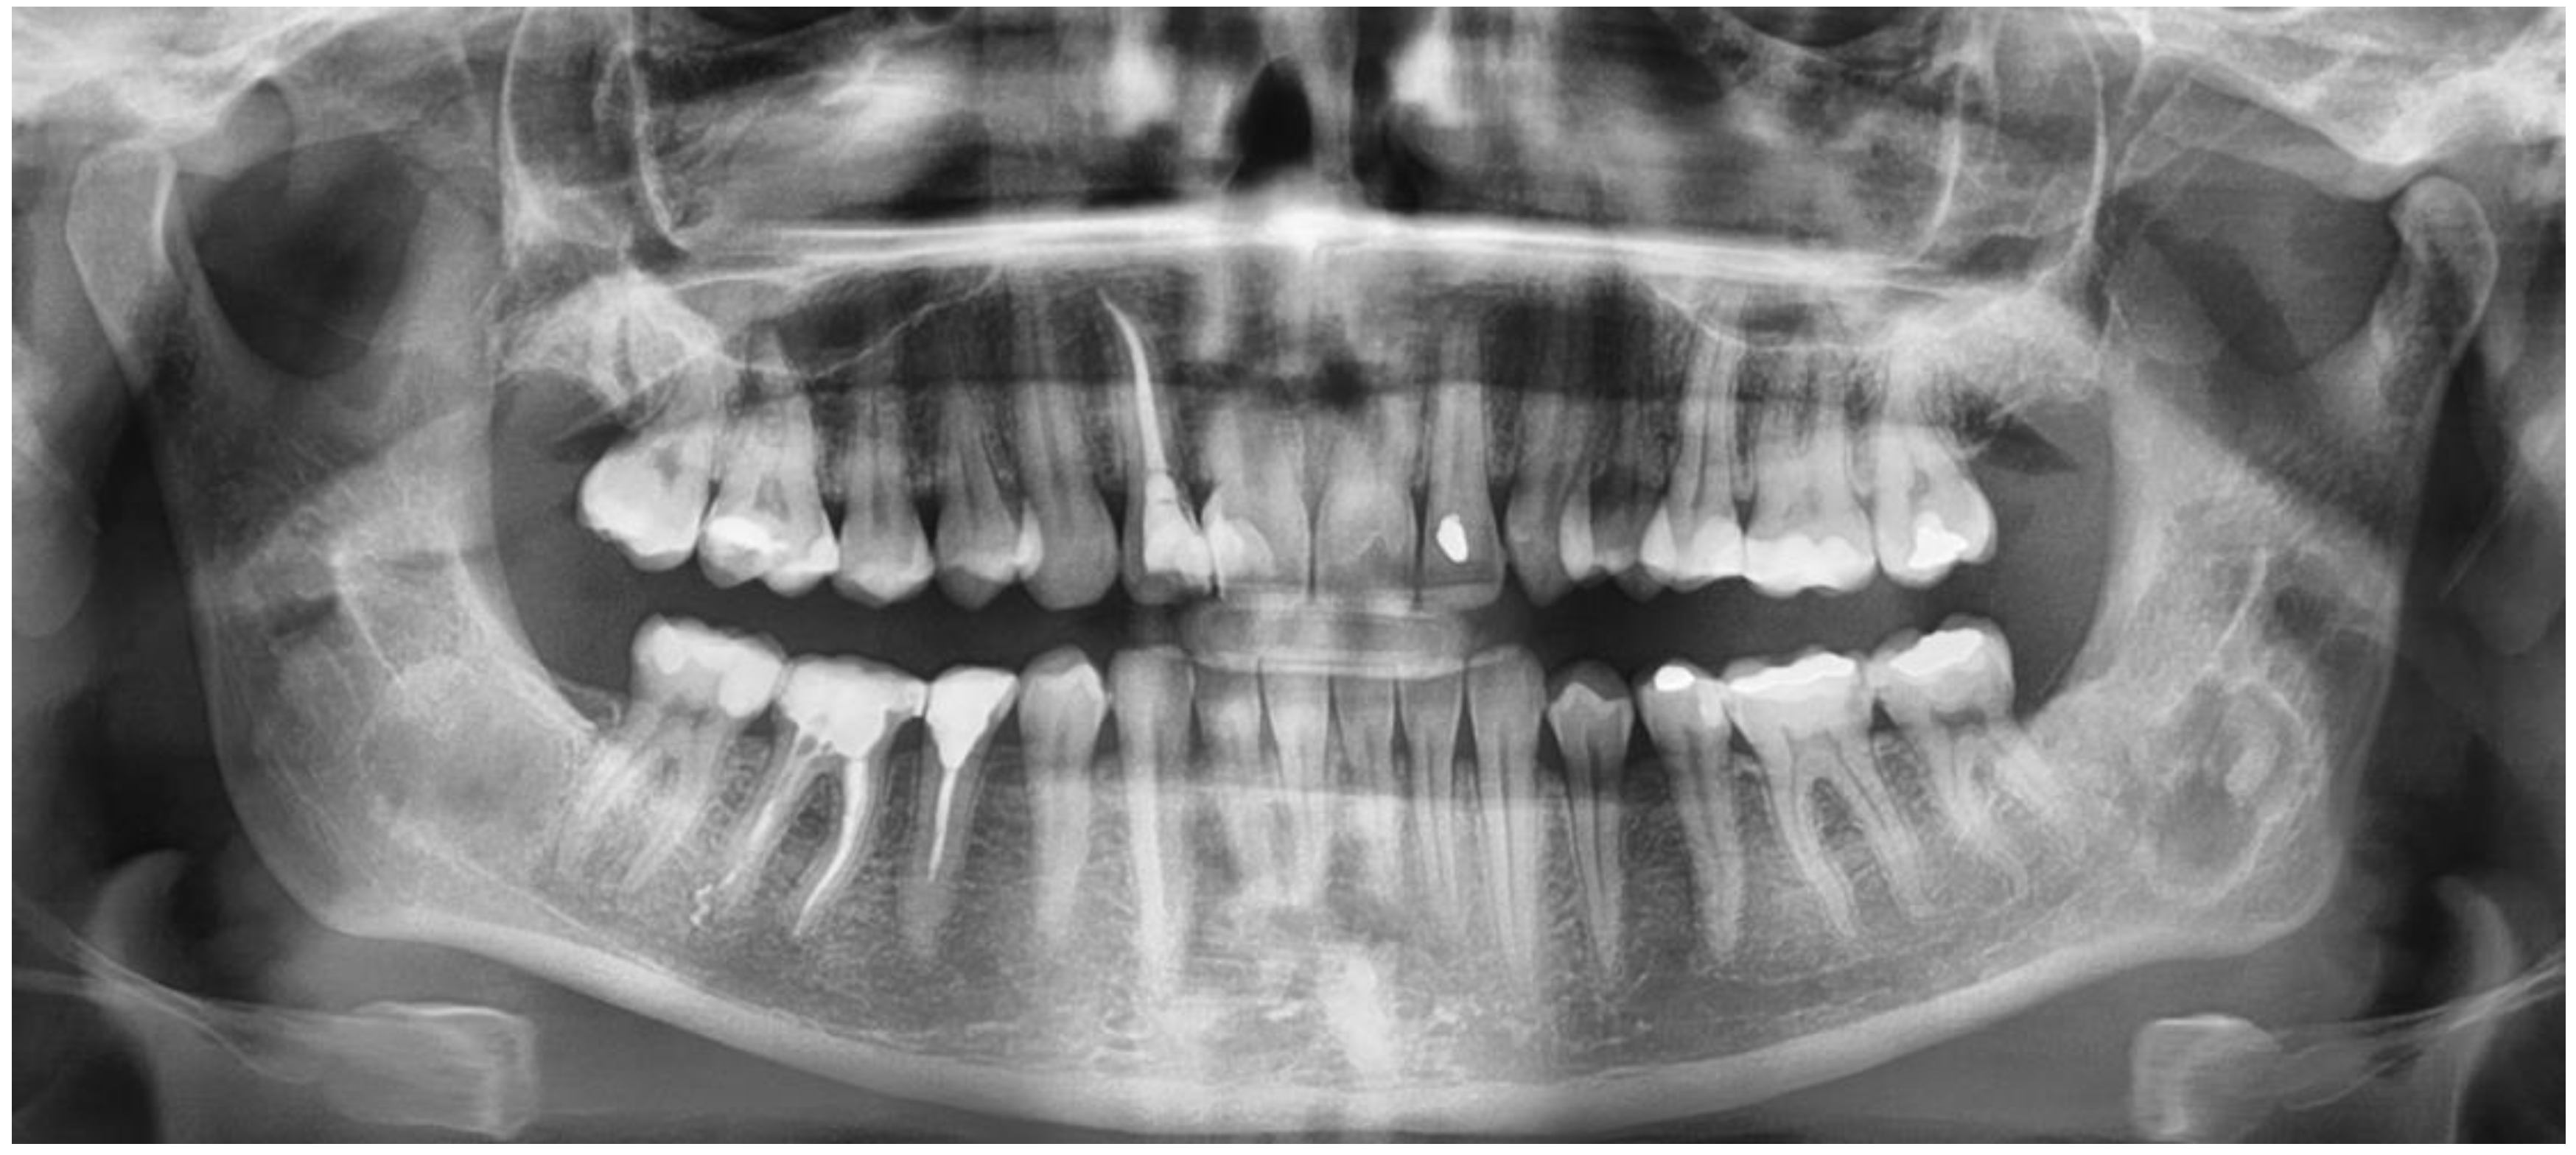

- mixed radiolucent/radiopaque lesion (depending on the stage of COD maturation), Figure 1.

- present in the jaw/maxilla in tooth-bearing areas, Figure 3